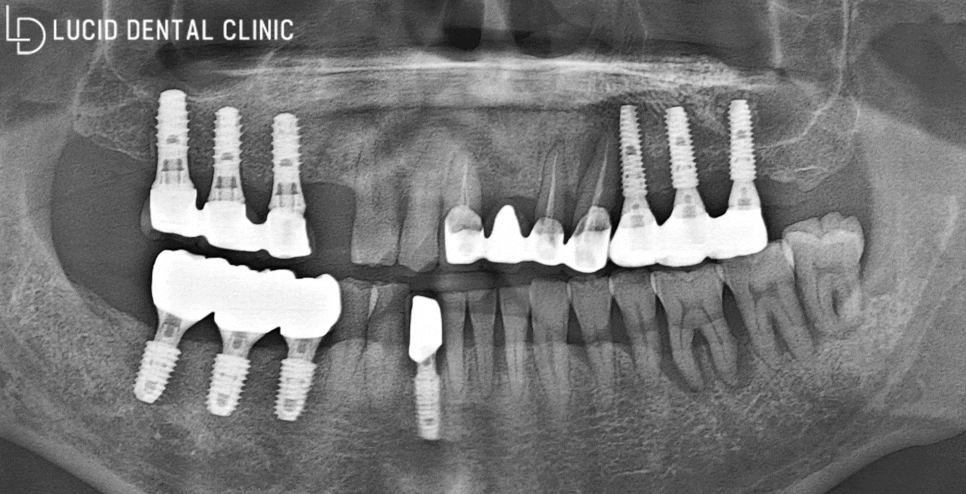

초진 파노라마 엑스레이 사진을 통해

정밀한 구강 검진을 시행하기로 했습니다.

- 전체 구강 현황은?

아래 보이는 사진이 바로,

파노라마 엑스레이입니다.

환자께서 주소로 말씀하셨던

(1) 발치 후 비어있는 어금니

부분을 발견할 수 있었는데요

문제는 그뿐만이 아니라

(2) 치근단 염증(뿌리 주위 염증)

(3) 빈 곳으로 인한 대합치 정출

두 가지의 문제점을 더 발견하여

상황이 좋지 않다고 판단하였습니다.

이대로 더 방치하게 된다면

정출이 더 심해져 자연스럽게

발치로 이어질 가능성이 있고,

치근단 염증 또한 근접치까지 영향을 주게 되어

다수의 치아 발치를 시행해야 될 수 있습니다.